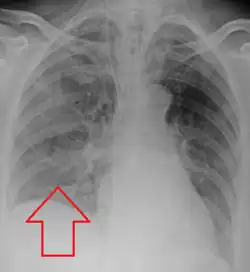

Aspiration pneumonia is typically diagnosed by a combination of clinical circumstances (people with risk factors for aspiration) and radiologic findings (an infiltrate in the proper location).[1] A chest x-ray is typically performed in cases where any pneumonia is suspected, including aspiration pneumonia.[18] Findings on chest x-ray supportive of aspiration pneumonia include localized consolidation depending on the patient's position when the aspiration occurred.[18] For example, people that are supine when they aspirate often develop consolidation in the right lower lobe of the lung.[18] Sputum cultures are not used for diagnosing aspiration pneumonia because of the high risk of contamination.[19] Clinical symptoms may also increase suspicion of aspiration pneumonia, including new difficulty breathing and fever after an aspiration event.[6] Likewise, physical exam findings such as altered breath sounds heard in the affected lung fields may also be suggestive of aspiration pneumonia.[6] Some cases of aspiration pneumonia are caused by aspiration of food particles or other particulate substances like pill fragments; these can be diagnosed by pathologists on lung biopsy specimens.[20]